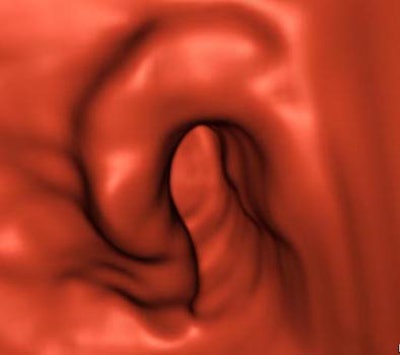

![]() |

| Three-dimensional MDCT endoluminal view shows the morphology of the stenosing lesion with excellent detail. Image courtesy of Dr. Riccardo Iannaccone. |